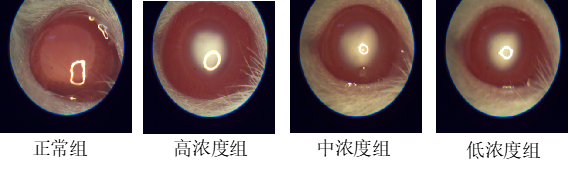

造模:SD乳鼠,模型组颈背部皮下注射给药,隔日注射一次,共注射三次,正常组等量注射生理盐水,7天后进行模型验证。

结果:正常组结构正常完整,无明显病理变化,模型组明显可见上皮细胞部分脱落,排列疏松,晶体边缘纤维肿胀,水肿细胞间有空泡形成;中高剂量组的造模效果相对而言要比低剂量好。

造模:SD大鼠,腹腔注射D-半乳糖溶液,连续注射数周。

结果:正常组样本晶状体上皮细胞排列整齐,无明显病理变化;模型组样本晶状体边缘细胞水肿,有空泡形成,晶体边缘纤维出现无形态水泥样,模型有效。